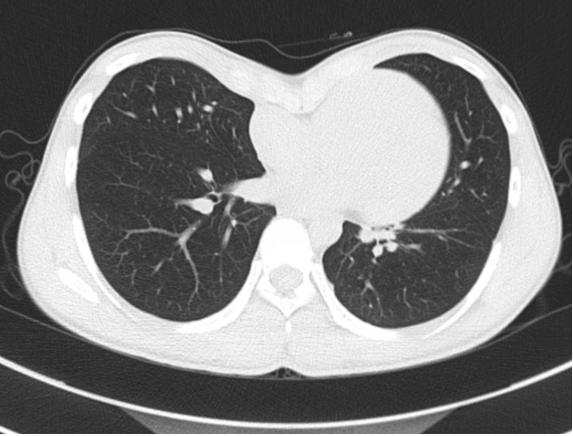

20岁小向(化名)胸前区凹陷畸形已有多年,被诊断为重度漏斗胸,心脏明显受压移位。小向今年已是大一学生,之前自己及家长对他胸前区的凹陷一直没有重视,上大学后自觉胸廓凹陷对其日常生活的困扰越来越显著并存胸闷不适,在了解到其胸廓畸形可手术治疗后经多方打听慕名来到我院就诊。就诊时的胸部CT显示:胸前区明显凹陷,凹陷最低点距离脊柱前缘5cm左右,心脏明显受压向左移位。

术前CT显示胸前区凹陷畸形导致心脏明显受压移位